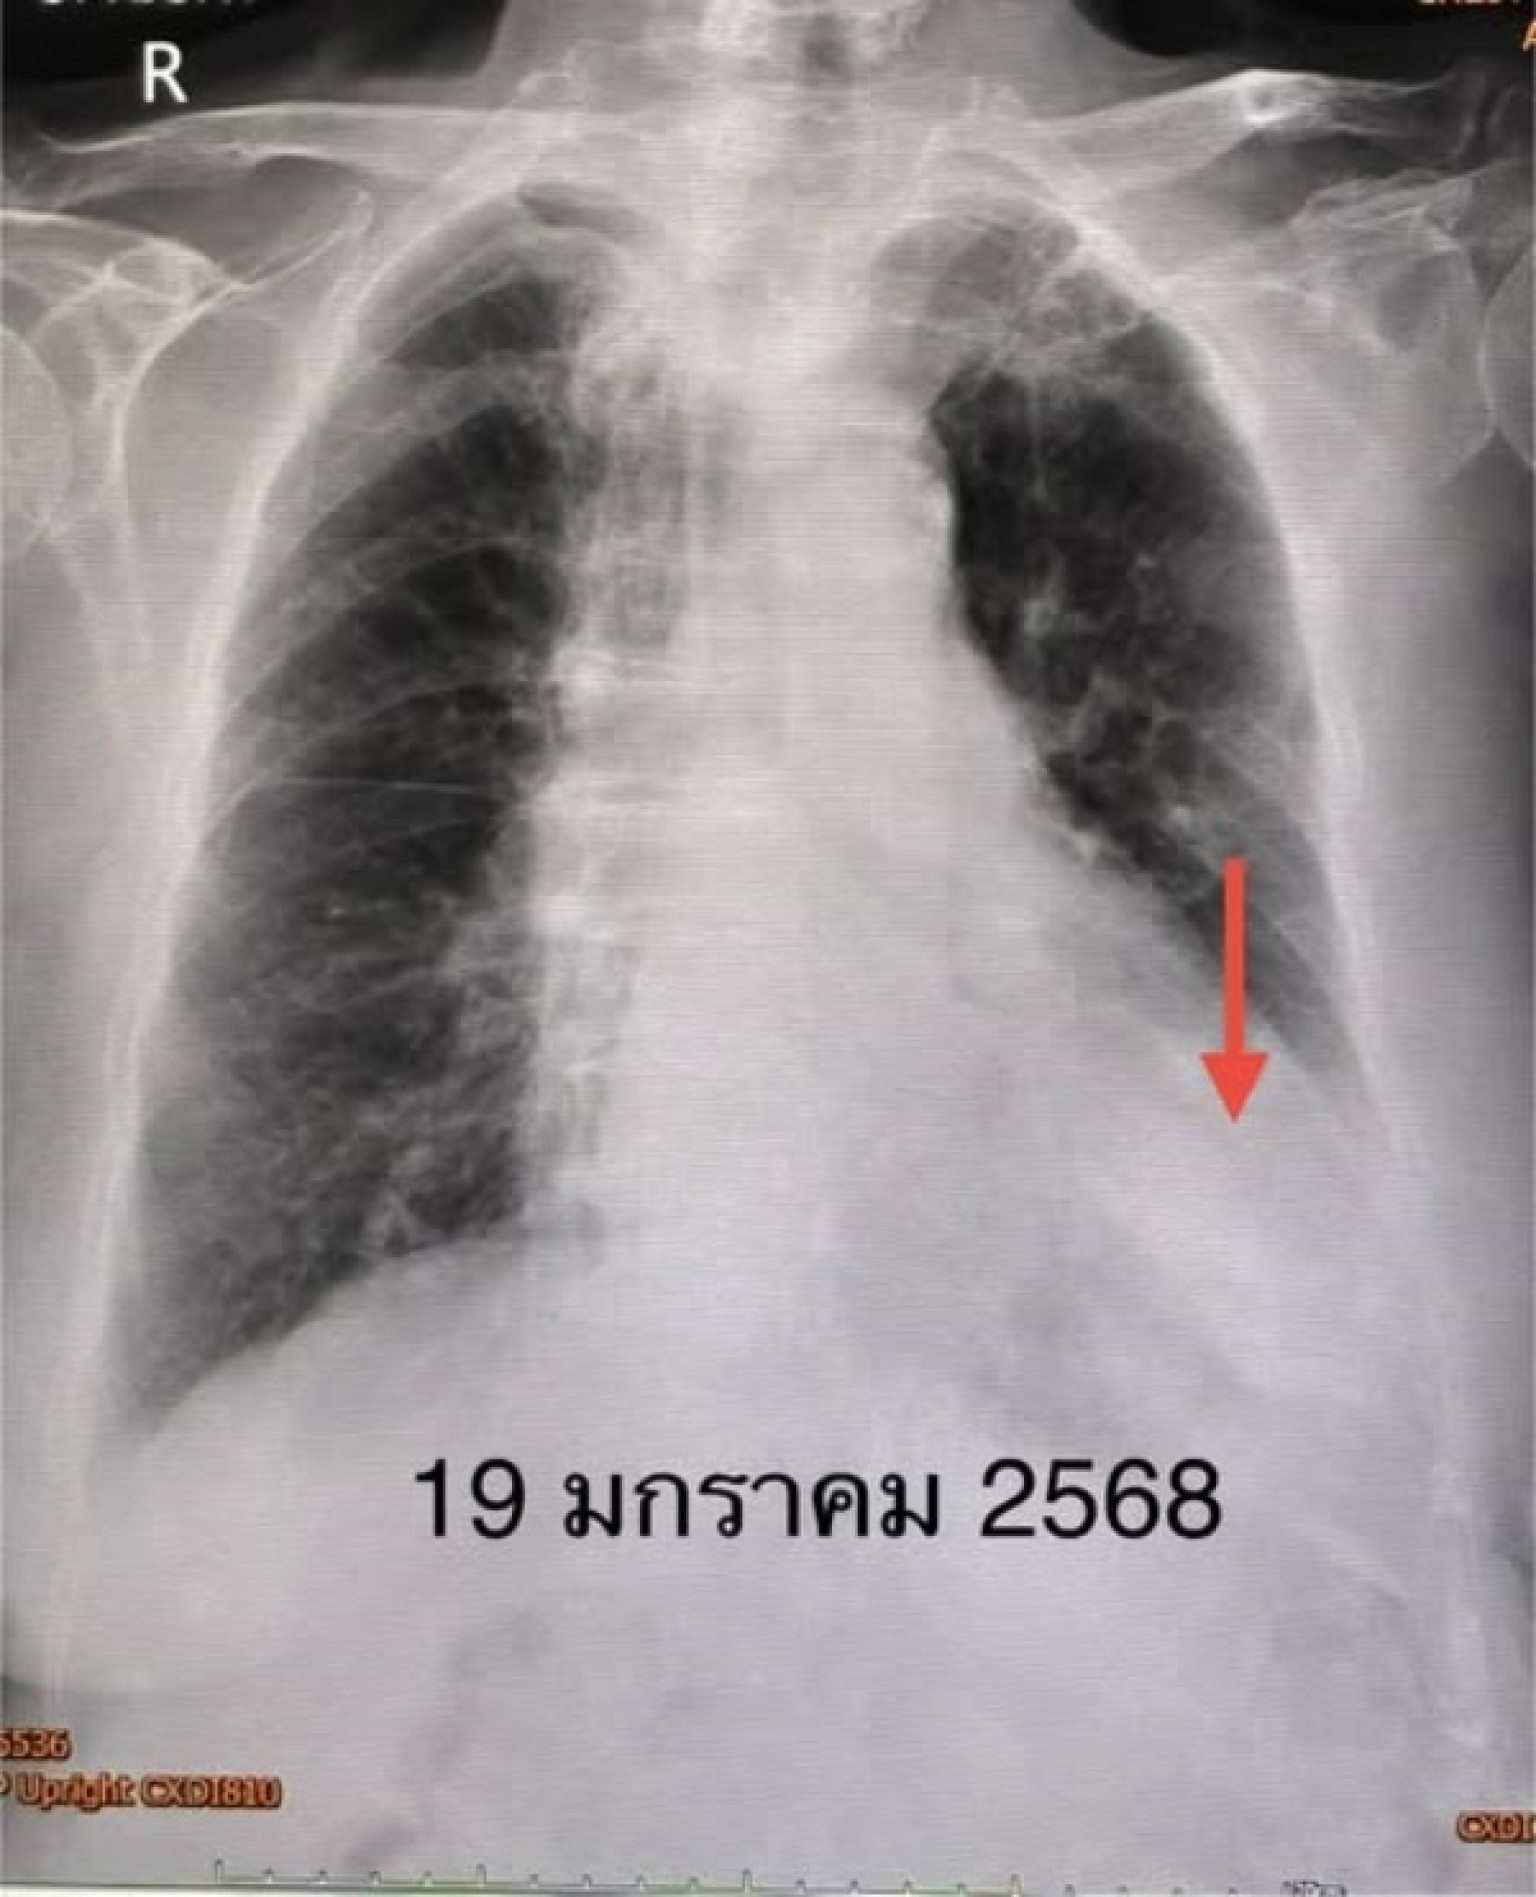

ตรวจร่างกาย ระดับออกซิเจนที่ปลายนิ้วต่ำ 87% ต้องให้ออกซิเจน 2 ลิตร/นาที ไม่มีไข้ ฟังปอดมีเสียงผิดปกติเล็กน้อยที่ปอดข้างซ้ายด้านล่าง เจาะเลือด เม็ดเลือดขาวในเลือดปกติ เอกซเรย์ปอดมีฝ้าขาวในปอดข้างซ้ายด้านล่าง (ดูรูป) ทำคอมพิวเตอร์ปอดยืนยันว่ามีฝ้าในปอดข้างซ้ายด้านล่าง และมีน้ำในช่องเยื่อหุ้มปอดเล็กน้อย (ดูรูป) ตรวจเลือดเม็ดเลือดขาวปกติ แยงจมูกส่งตรวจรหัสพันธุกรรมเชื้อ 22 สายพันธุ์ไม่พบเชื้อ ส่งเลือดตรวจ Legionella pneumophila Antibody IgM positive 1:200